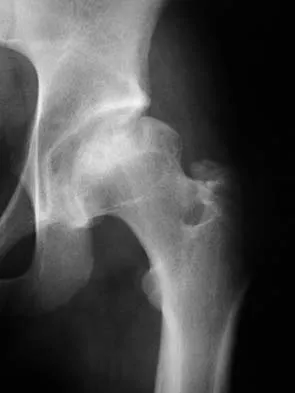

Which of the following choices best describes the fracture pattern shown in Figures 2a through 2c?

The fracture pattern shown in the radiographs is a fracture of the posterior column. The only line interrupted on the AP pelvis is the ilioischial line. The obturator oblique view shows that the iliopectineal line is intact as is the outline of the posterior wall. The iliac oblique view shows an interruption of the ilioischial line and an intact anterior wall. Therefore, this fracture is a fracture of the posterior column. Letournel E, Judet R: Fractures of the Acetabulum, ed 2. Berlin, Germany, Springer Verlag, 1993.

- Matta J: Surgical treatment of acetabular fractures, in Browner BD, Jupiter JB, Levine AM, et al (eds): Skeletal Trauma, ed 3. Philadelphia, PA, WB Saunders, 2003, vol 1, pp 1009-1149.